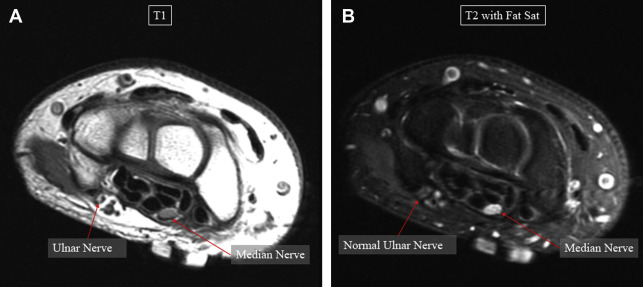

The mainstay of MRN is the identification of peripheral nerve anatomy and pathology using T1-weighted and T2-weighted fluid-sensitive (eg, short tau inversion recovery [STIR]) sequences, which are analyzed to understand nerve signal intensity, size and caliber, course, fascicular pattern, perineural tissues, and nerve-associated mass lesions. Imaging is generally performed on scanners with 1.5- or 3-T (T) magnets using phased-array surface coils shaped around the area of interest to increase signal-to-noise ratio and parallel imaging that allows for precise localization of the magnetic resonance signal. Normal nerves display an intermediate signal intensity similar to muscle on T1-weighted images and intermediate to slightly increased intensity on T2-weighted images, depending on the amount of background fat suppression and the presence of endoneurial fluid. Obtaining fat-saturated images is extremely important when trying to image nerves ( Fig. 1 ). Healthy peripheral nerves do not normally enhance with gadolinium contrast because of the presence of the blood-nerve barrier. Contrast administration may assist in cases where there is suspicion for infection, inflammation, diffuse lesions, or tumors, or in physical injury, where nearby denervated muscles may also demonstrate contrast enhancement. Thus, in the authors’ opinion, contrast should be given for all MRN studies, unless there is a specific contraindication. In abnormal nerves, the most common and easily identifiable change is an increase in the signal intensity of the nerve on T2-weighted images, approaching the intensity of adjacent blood vessels.